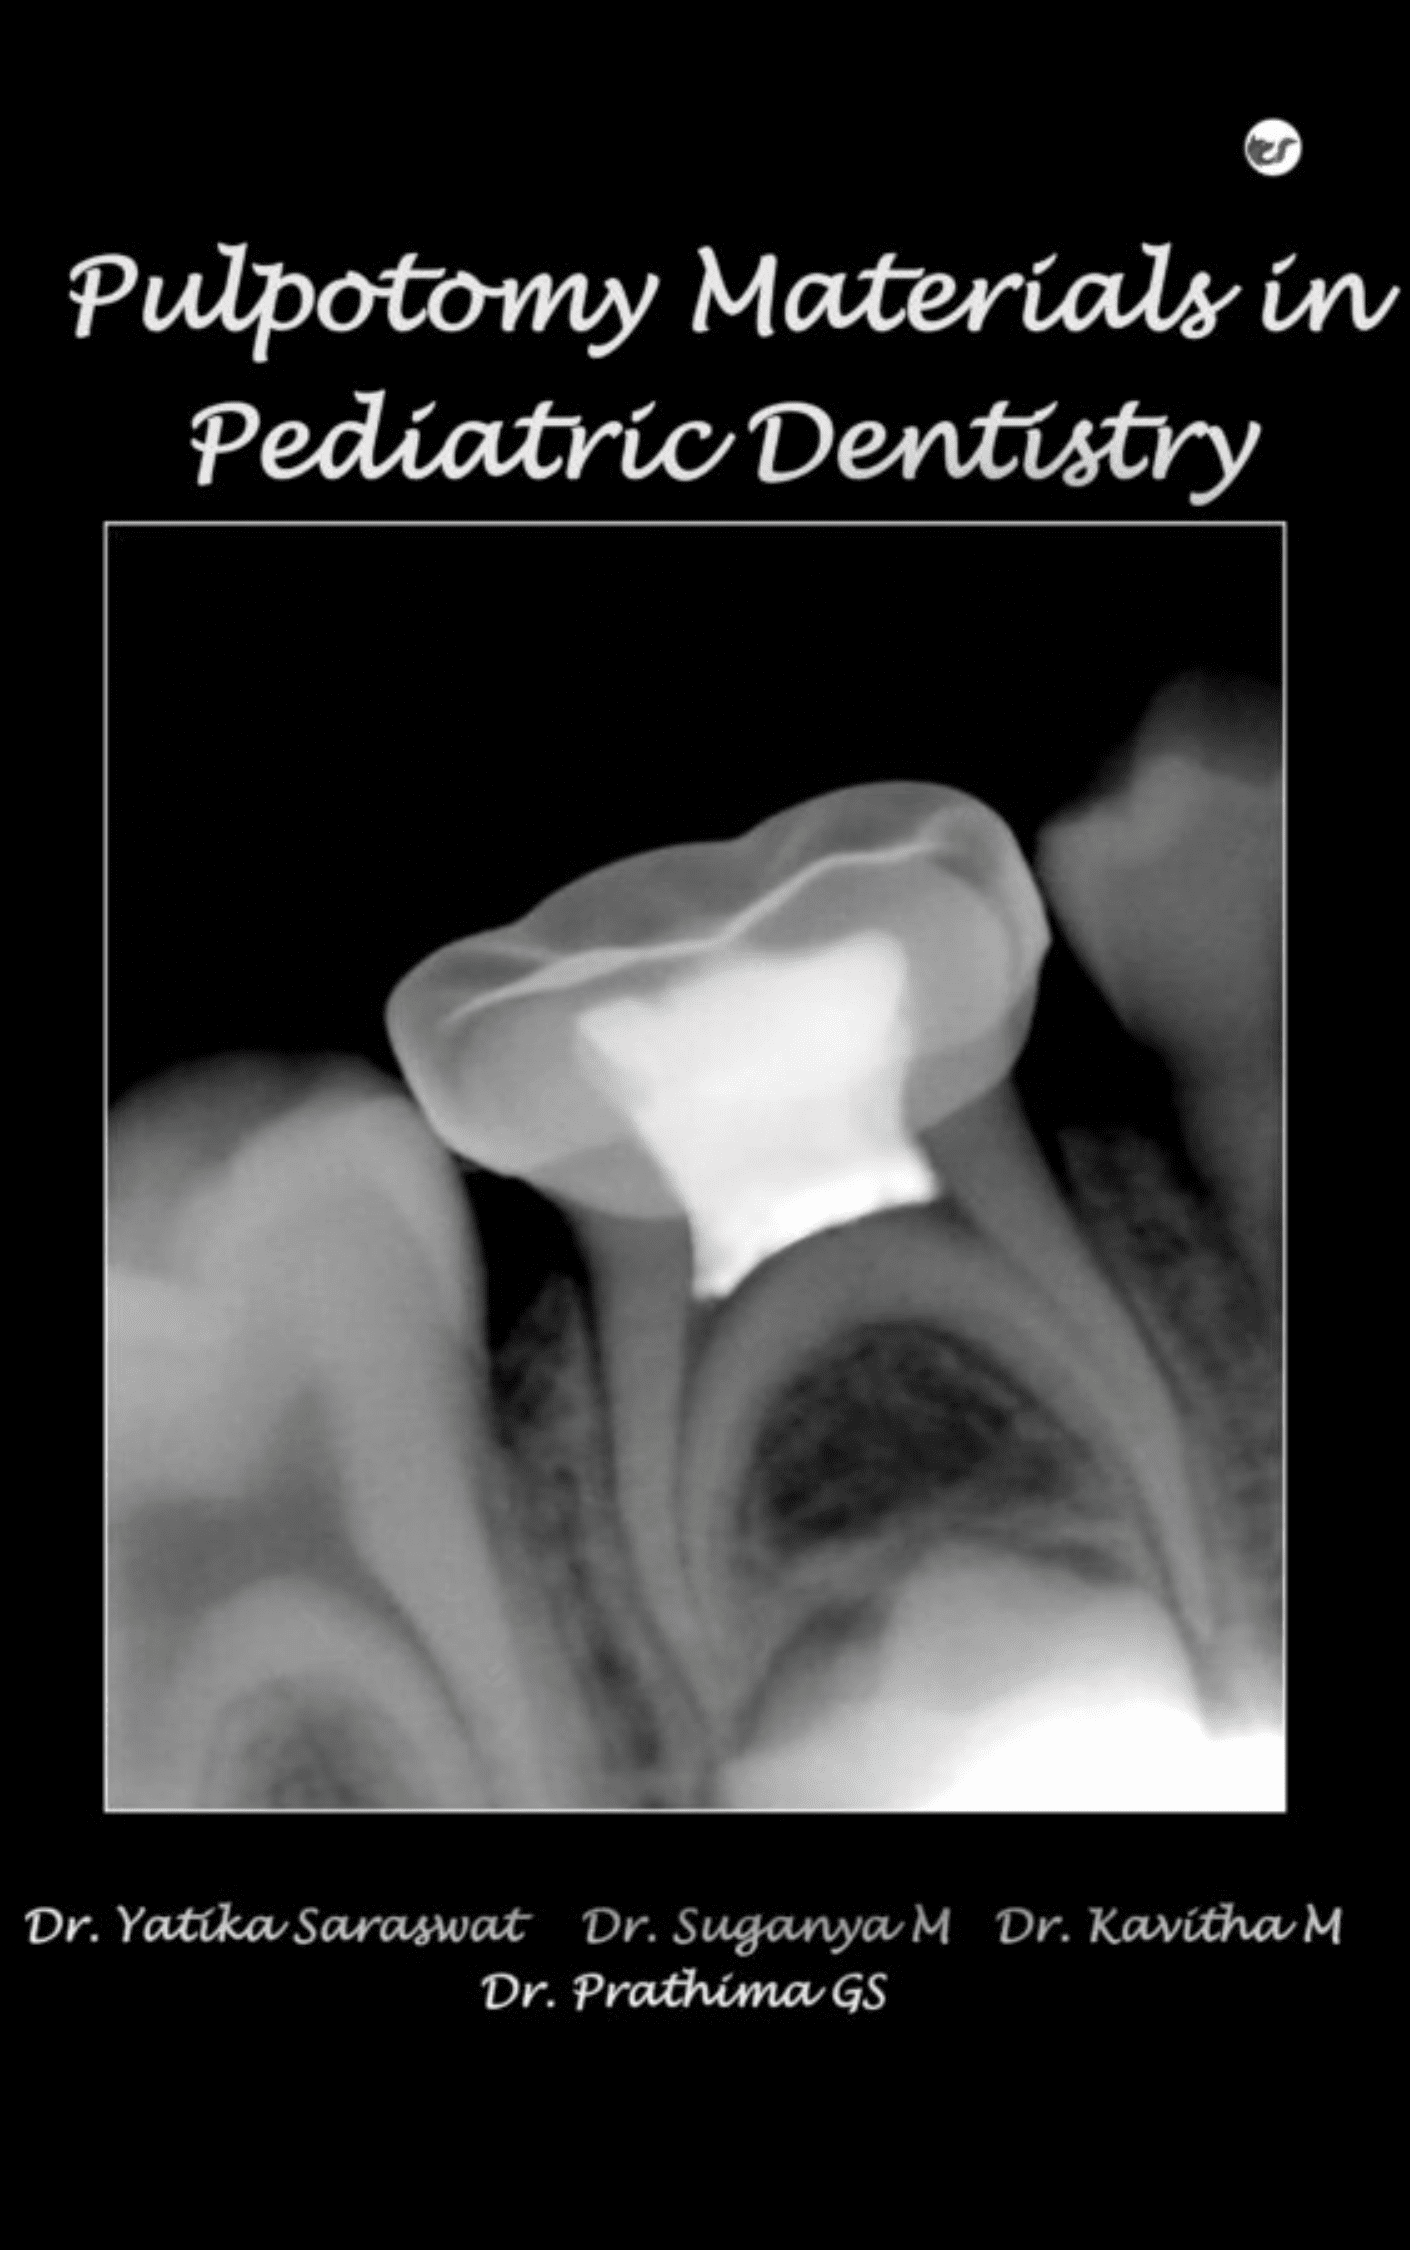

Pediatric dentistry aims to maintain the deciduous teeth in their position until the permanent teeth erupt. The deciduous tooth plays an important role in mastication, digestion, maintenance of arch integrity, stimulation of jaw growth, development of speech and esthetic function. Pulpotomy is one of the vital pulp therapy techniques used for preserving decayed primary teeth with extensive caries but without evidence of any radicular pathology. It is a procedure in which a part of an exposed vital pulp is removed, usually by preserving the vitality and function of the remaining part. Various Pulpotomy materials have been introduced in Pediatric dentistry so as to make the pulpotomy procedure both clinically and radiographically successful. This monograph highlights various Pulpotomy materials, their indications, contraindications, techniques of application along with the recently introduced pulpotomy materials.

Pulpotomy Materials In Pediatric Dentistry